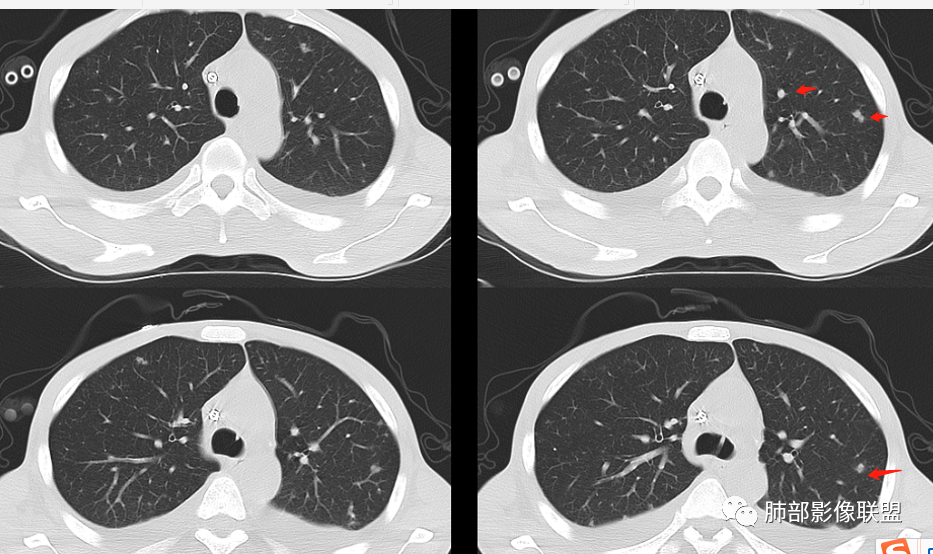

2、两肺多发结节,中上肺分布为主,结节边界尚清,部分边界平直

3、左上叶下舌段见沿支气管走形斑片状高密度影,边界模糊

从整体表现,结节的边缘、形态,片状影的改变——支持炎性

2.双肺散在不规则小片状影及结节影,部分可见磨玻璃晕。结节影边界较清楚。左肺片影边界不清,范围较大,支气管相关,支气管壁增厚不明显,病灶内见液化空洞。

3.肺炎型肺部影像学表现常为双肺多发片影,肉芽肿样结节影,边界相对清楚,可见磨玻璃晕,部分病灶可显示坏死空洞。部分病例出现胸水。支气管炎型病例可见较广泛支气管壁增厚。